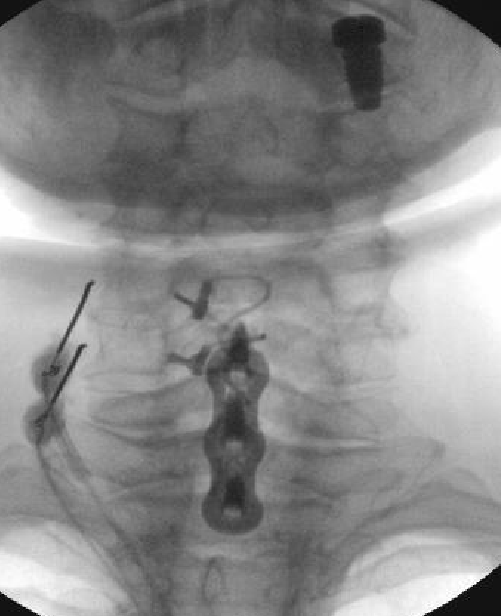

Nasty neuritis. This is 80 degrees 90 seconds.

These images look great. Sorry it happened? Steroid?

Lyrica Rx sent in, and we're starting it for chronic pain (and neuritis). She gets a shoulder scope in two weeks for a large RCT. I like antineuropathics (gabapentin 100mg HS or BID) perioperatively in general. I wish they were given 2 weeks before and after ALL orthopedic surgeries.

Dexamethasone given before RFA needles were removed.